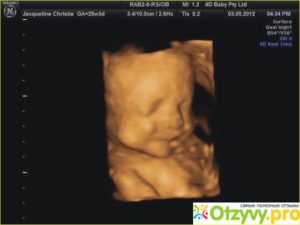

На 28 неделе ребенок весит до 1 кг и имеет рост 35 см. На УЗИ видно, что плод улыбается, сосет палец, хватает себя на ножку.

С каждым днем кроха видоизменяется. На 34 неделе беременности УЗИ позволяет увидеть индивидуальные черты ребенка и даже определить, на кого он похож. Следует отметить такие явные изменения:

Вес ребенка на 34 неделе беременности может достигать 2,5 кг, а рост составлять 45 см. Очень интересно знать, как выглядит малыш на данном сроке. 34 недели беременности — это примечательный срок, когда малыш продолжает активно расти и развиваться.